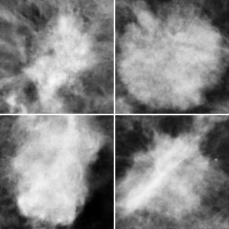

Fig. 2(a) shows two synthetic masses (left column) and two real masses (right column) depicting that DCGAN could generate visually-similar masses to the ones it was trained on. Moreover, Fig. 2(b) shows the F1 score for different training sizes, where each line represents one augmentation approach. The blue line (ORG) shows the classification results using the original unbalanced training dataset. As more training images are available, the classifier increases its performance until k=750 where the performance saturates. When comparing the blue and the green lines (GAN), the latter shows faster improvements which shows that the generator has learned to unlock unseen images in the real distribution helping the classifier to distinguish masses among normal tissue. If, on the other hand, the original data is augmented using horizontal and vertical flipping (the orange line of Aug ORG), the classifier performs similarly to GAN (green) at medium sizes. Finally, the red line (Aug GAN) shows the F1 score when random online flipping was applied on the combined real and synthetically-generated images. As can be depicted in the figure, Aug GAN outperformed all other modes at any k, except a negligible drop at 1,300, with the maximum improvement at 250 with about 0.09 over ORG approach.